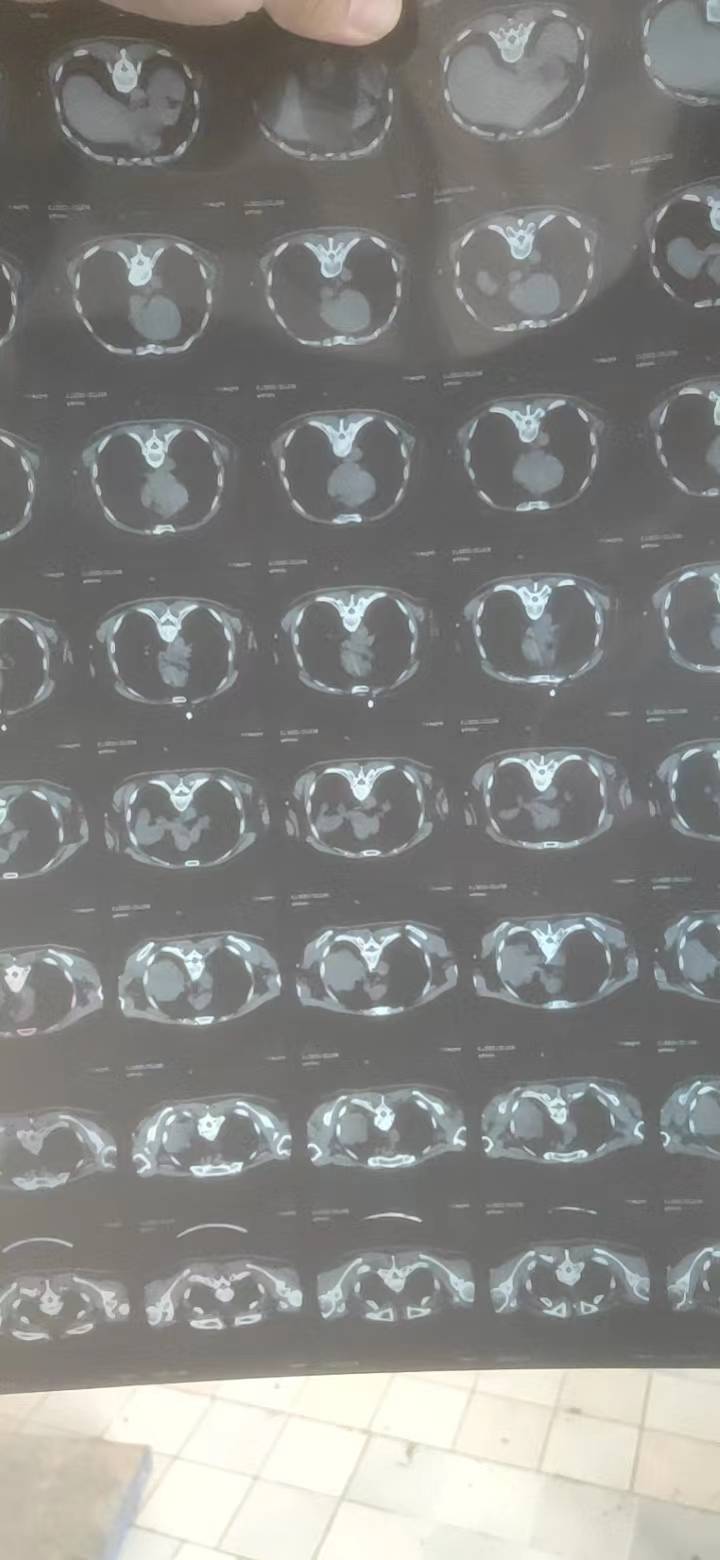

手术目前就不用考虑了,至少是3期了,还是寻求化疗和靶向治疗

局部晚期,有转移了肯定不能直接手术了,一般可以这样理解,就是气管镜够得到的话就是中央型(当然有些情况是肿瘤太大可以够到,但是实际附着区域可能在周围?),血管分布就是从心脏大血管向两肺分支,可以去搜下肺血管的解剖图,结合肿瘤部位自行想象这个距离(这么大的肿瘤一般都靠近大血管的,很考验外科医生的水平